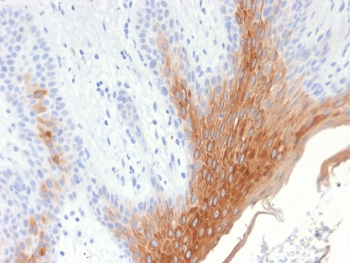

This mAb recognizes a protein of 56.5kDa, identified as cytokeratin 10 (CK10). CK10 is expressed in all suprabasal layers of the epidermis. In the epidermis, expression of CK10 strictly parallels the extent of differentiation; it is absent in the basal layer, appears in the first suprabasal layers and increases in concentration towards the granular layer. However, CK10 is rarely detected in early stages of vulvar squamous carcinomas (tumors less than 2 cm, clinical stage I) regardless of the tumor grade. In larger and more advanced tumors (greater than 2 cm, clinical stages II and III), CK10 is detected very frequently. Expression of CK10 is related to maturation of malignant keratinocytes, being preferentially detected in more-differentiated parts.